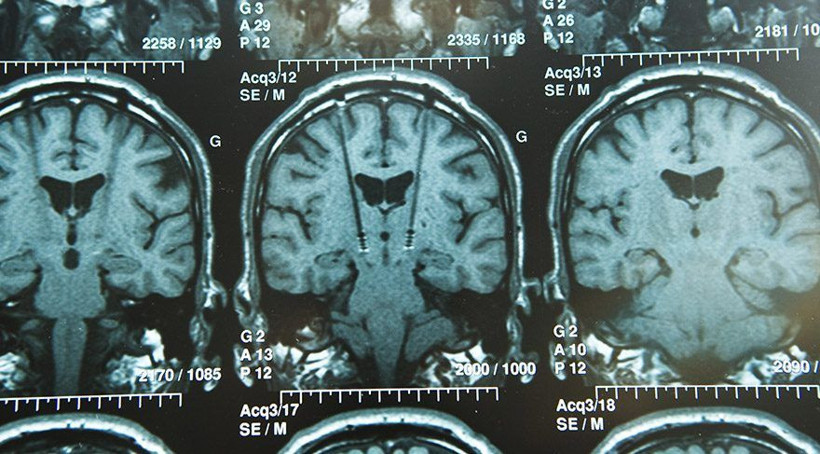

Beyin vücudumuzun en önemli organlarından biri arasında yer alıyor. Beyin sağlığı bozulduğunda vücudun dengesinde de problemler ortaya çıkabiliyor. Beynimiz gün içinde yaptığımız alışkanlıklar yüzünden hızla yaşlanabilir ya da günlük hayatta tükettiğimiz besinler beynimizi doğrudan etkileyebilir. Bazı besinler beynimiz için büyük fayda sağlarken bazı besinler de beynimize doğrudan zarar vermektedir. Peki beyin sağlığımız için hangi besinler tüketmeliyiz ve hangi besinleri tüketmemeliyiz? İşte beyin sağlığımızı etkileyen yararlı ve zararlı besinler...